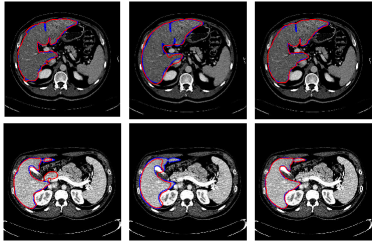

Figure 6: Illustrations of the role of the likelihood liver map. From the first column to the last, outcomes of graph cut without the likelihood liver map, convolutional neural networks and the proposed integrated model for two typical images are displayed respectively in red. The ground truth is in blue

To better understand the role of the learned liver likelihood map, Fig. 6 depicts the outputs of the graph cut without the liver likelihood map, 3D CNNs and the proposed method for two typical images in red. The ground truth segmentations drawn by experts are in blue. Obviously, incorporated with the liver likelihood map, the proposed model can achieve a better agreement with the ground truth.